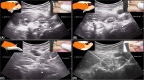

Ultrasound imaging and guided hydrodilatation for the diagnosis and treatment of internal snapping hip syndrome